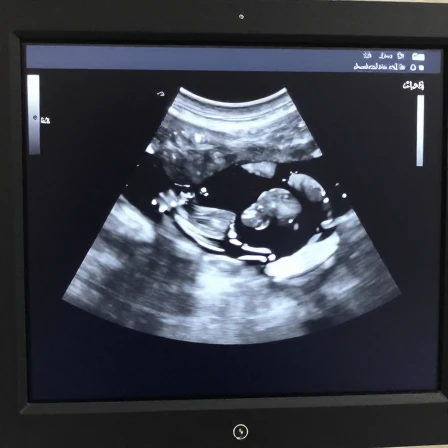

سونوگرافی جنسیت

سونوگرافی

1404/11/16

مقدمه: اشتیاق به دانستن جنسیت جنین سونوگرافی جنسیت یکی از هیجان انگیزترین مراحل دوران بارداری برای والدین است. ا...